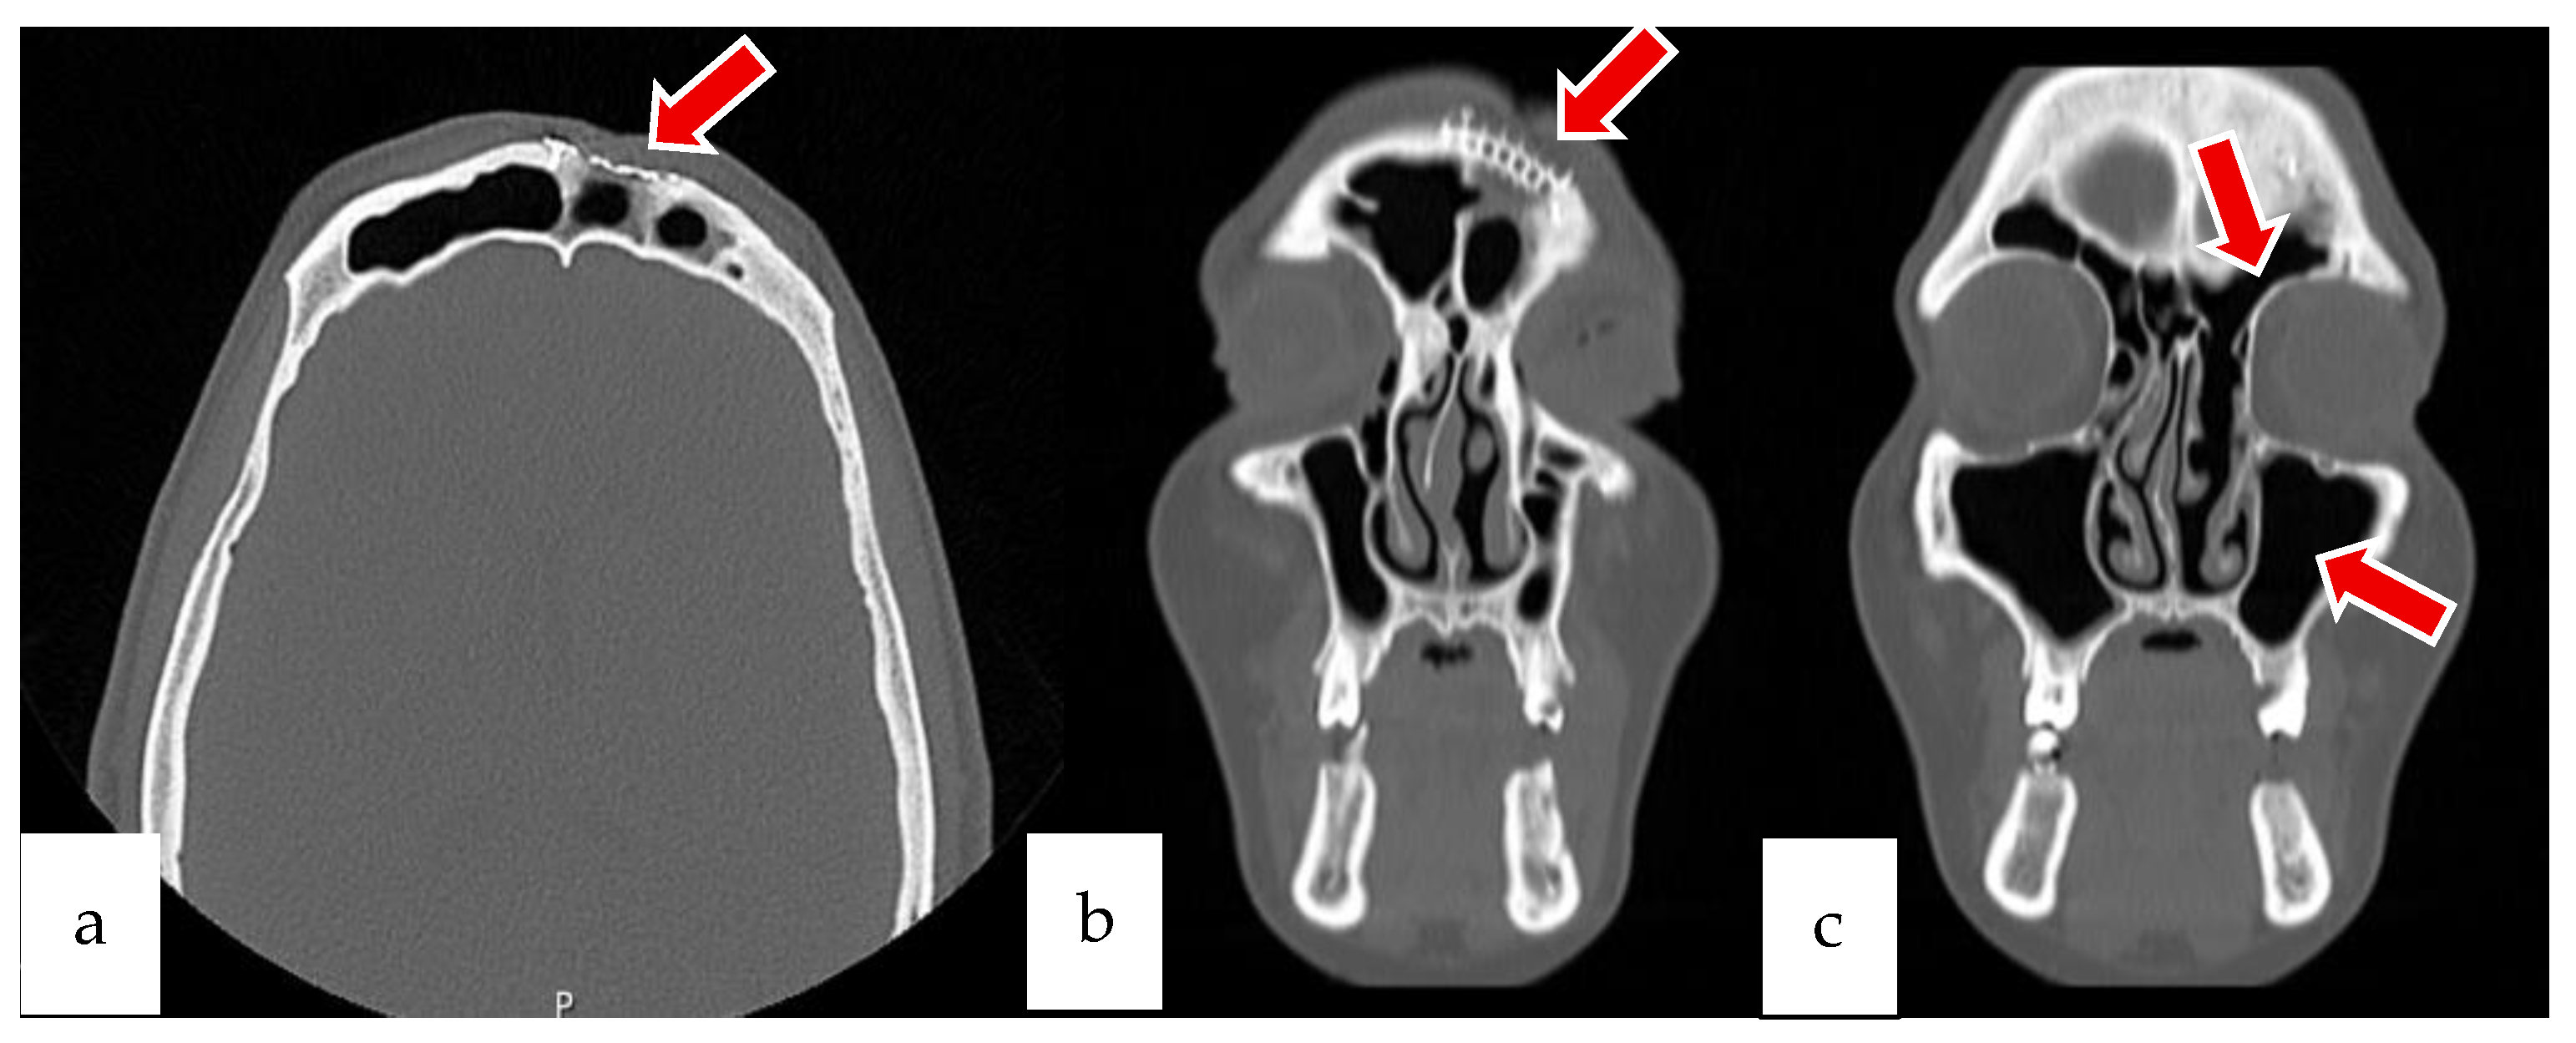

2.1. Case 1

2.2. Case 2